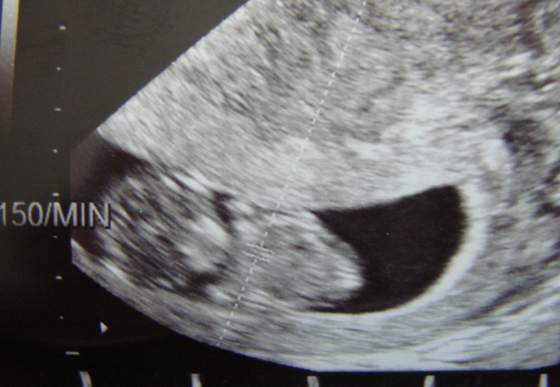

Nie, kręcił sie, przekręcał. USg troszkę potrwalo zanim go dr zmierzył ;) ale nie skakał tak jak córeczka ;) bo ona skakała jak kangurek. tyle ze jak przyglądnę sie USG jej i teraz to wtedy jakby było duuuzo miejsca w macicy

DSC02419.jpg to Kingusia mając 9 tygodni i 5 dni :)

• DSC02419.jpg

DSC02419.jpg

21,1 KB · Wyświetleń: 62